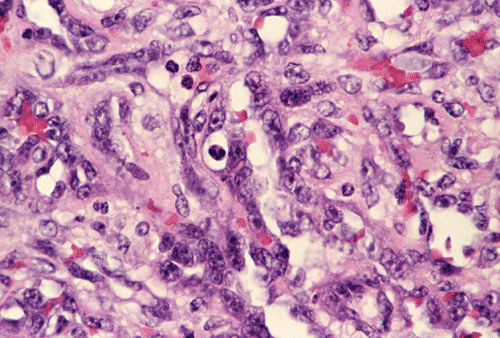

Panel A, B and F are taken from the dermal-epidermal junction. Panel B, C, D, and E are taken from the same area. Panel F, G, H, and I are taken from the same area

The tumor appears to be centered on the dermis and does not involve breast parenchyma in the sections examined A (not shown). On low-magnification (Panel A, B and F), the lesional tissue is a highly cellular and vascular tumor in the dermis. The large areas of hemorrhage ("blood-lake") and dilated vascular channels (Panel A, and F) probably correspond to the "red nodules and yellow patches" on physical examination. Although the tumor extends deeply into the subcutaneous tissue (not shown here), there is no evidence of invasion in to the epidermal layer (Panel A, B and F). The histology of this tumor varies in different areas. In some areas, it appears as a densely packed spindle cell tumor with exuberant and irregular and anastomosing vascular channels (Panel B, C, and D). The endothelial cells protrudes into the vascular channels and had enlarged, hyperchromatic nuclei with  prominent nucleli. In another area, the lesion contains numerous ectactic and anastomosing vascular channels (Panel F, G, H, and I). Pleomorphic changes are also prominent in the vascular cells in these areas. On immunohistochemistry, the tumor cells are immunoreactive for CD31, CD34 (not shown).

The most distinctive histologic feature in angiosarcoma is the formation of irregular, anastomizing vascular channels lined by plump, hyperchromatic, and anaplastic endothelial cells. These vascular channels proliferate and infiltrate the glandular breast tissue, fat and subcutaneous tissue.  Low-grade lesions usually have only rare mitotic figures. Increased mitotic activity in an otherwise low-grade angiosarcoma may suggest the presence of a high-grade lesion in adjacent tissue.  Intermediate-grade lesions have an increased amount of endothelial tufting and papillary formations within the irregular vascular channels and these are associated with increased numbers of mitoses. While the anastomizing vascular channels are characteristic of areas with low- or intermediate- grade cytologic features, solid sheets of spindle cells with minute, slit-like channels not filled by red blood cells are common in high-grade areas. In addition, high-grade angiosarcoma are marked by numerous mitotic figures in all parts of the tumor, the presence of “blood lakes”, and necrosis.  In most tumors the high-grade portion comprises the core of the tumor and the better-differentiated portion forms the infiltrative border of the lesion 3.